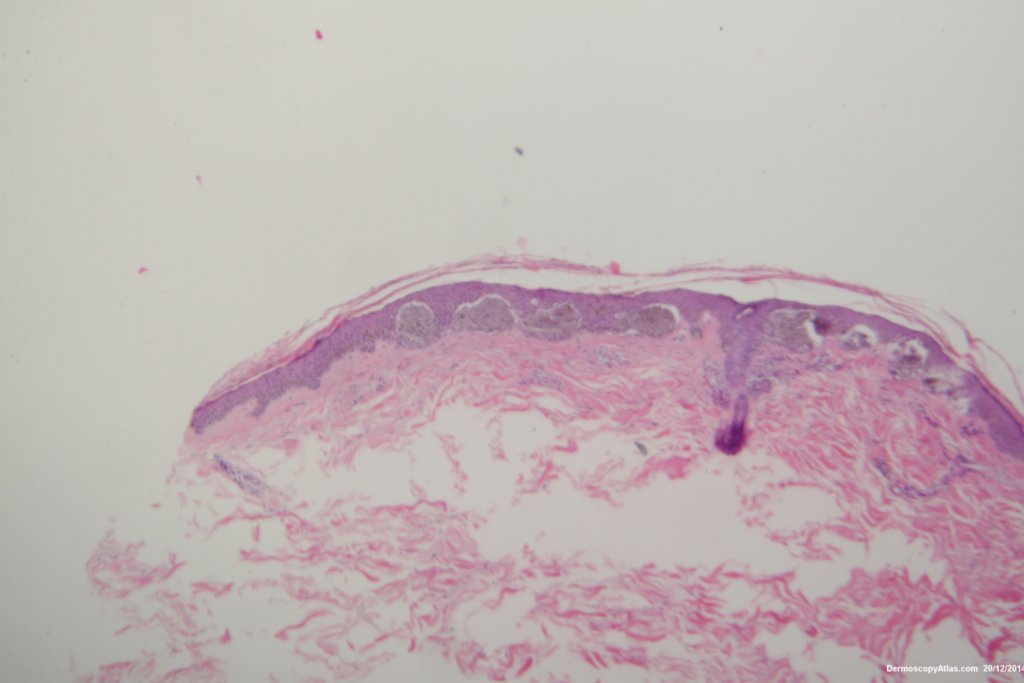

The histopathology shows nests of epitheliod and spindled cells with lots of melanin in them. There are a few melanophages in the dermis. There is no inflammatory reaction beneath this lesion. There were no mitoses. This is just a junctional lesion ie no nests of cells in the dermis.